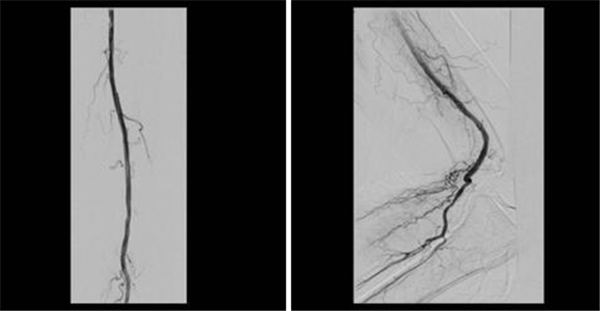

支架置入后再造影,可见血液顺畅通过,也不影响膝关节弯曲活动,如图~